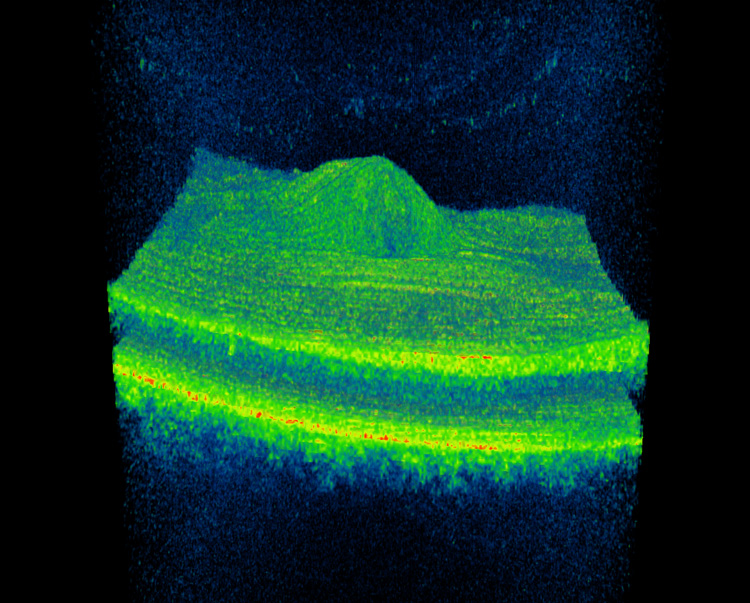

Tomografia 3D macular

Tomografia macularRetinografia blog Autor: Jorge Haro López. Colegiado: 9653